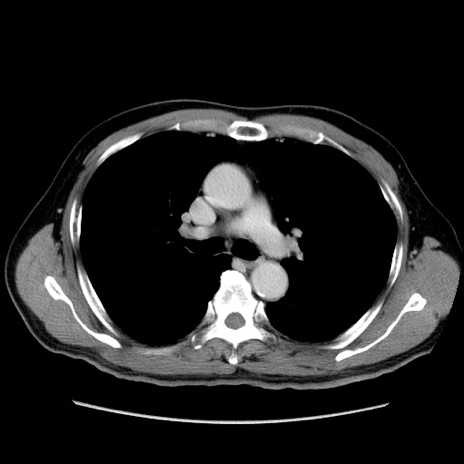

症例34(横断像)

【症例】60歳代 男性

【主訴】右鼠径部膨隆

【現病歴】1年程前より右鼠径部膨隆あり。自己にて還納可能だったため放置していた。3時間前より右鼠径部の脱出を認め、還納困難となり受診。

【既往歴】高血圧

【身体所見】右鼠径部に小児頭大の膨隆あり。弾性硬であり、用手還納は困難。左鼠径部にも膨隆を認める。脱出はなし。

【データ】WBC 15500、CRP 測定なし